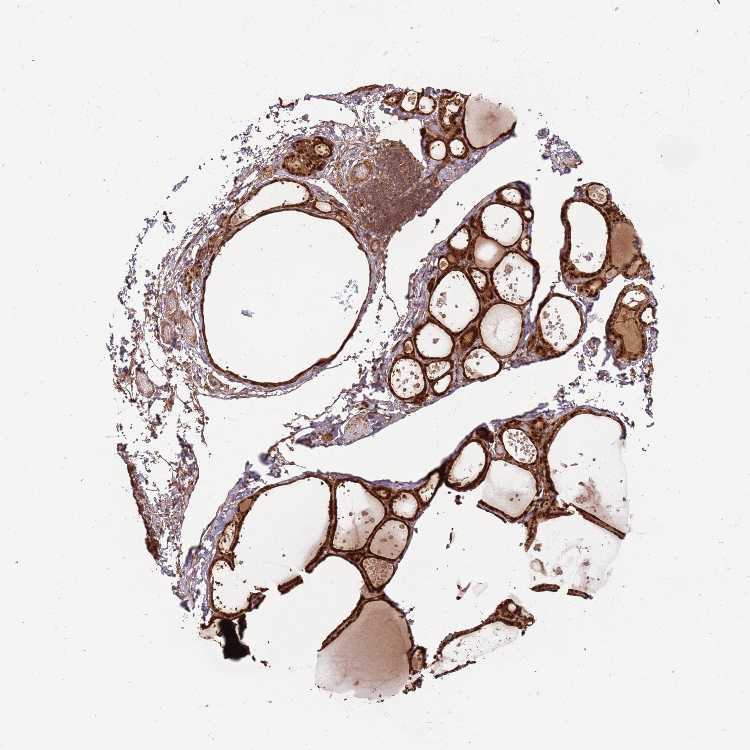

PGLS